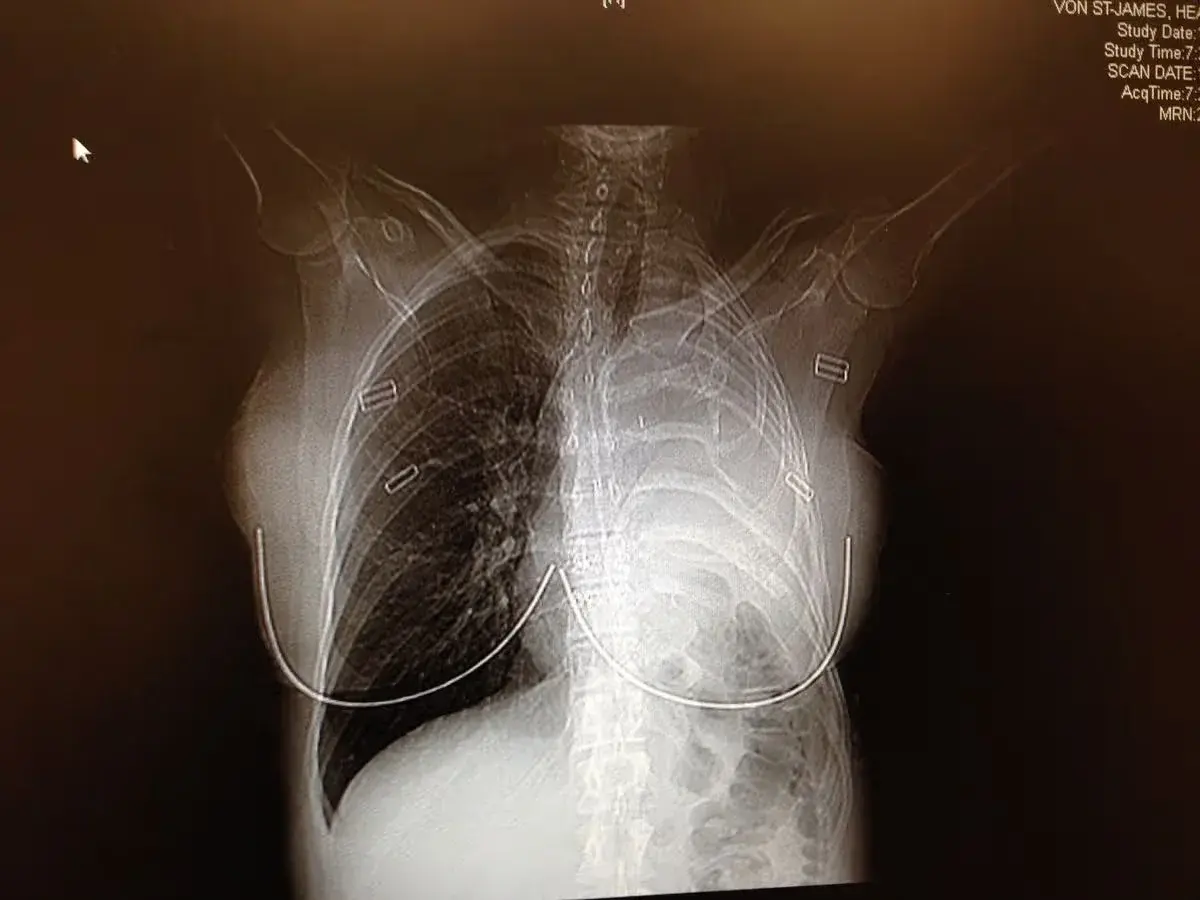

หลังจาก "เฮเธอร์ วอน เซนต์ เจมส์" เข้ารับการตรวจหลายอย่าง รวมถึงการสแกน CT แพทย์พบเนื้องอกใกล้ปอด และ ภายใน 2 สัปดาห์ก็ได้รับการวินิจฉัยว่าเป็น "มะเร็งเยื่อหุ้มปอดชนิดเมโซเธลิโอมา" ซึ่งเป็นมะเร็งรุนแรงที่เกิดจากการสัมผัสแร่ใยหิน

อย่างไรก็ตาม "เฮเธอร์ วอน เซนต์ เจมส์" ไม่ยอมแพ้และตัดสินใจต่อสู้กับโรคอย่างเต็มที่ โดยเธอถูกส่งตัวไปพบผู้เชี่ยวชาญในเมืองบอสตัน และ ต้องเข้ารับการผ่าตัดใหญ่ โดยแพทย์ได้ตัดซี่โครงออก 1 ซี่ ปอดซ้าย เยื่อหุ้มปอด เยื่อหุ้มหัวใจ และ บางส่วนของกระบังลมออก ก่อนจะใช้วัสดุสังเคราะห์ทดแทน และ หลังการผ่าตัด เธอได้รับเคมีบำบัดแบบให้ความร้อนในช่องอก รวมถึงเคมีบำบัดและการฉายรังสีเพิ่มเติม ซึ่งผลการรักษาประสบความสำเร็จ โดยไม่พบเซลล์มะเร็งหลงเหลืออยู่ และ เธอก็ปลอดมะเร็งมาจนถึงปัจจุบัน...